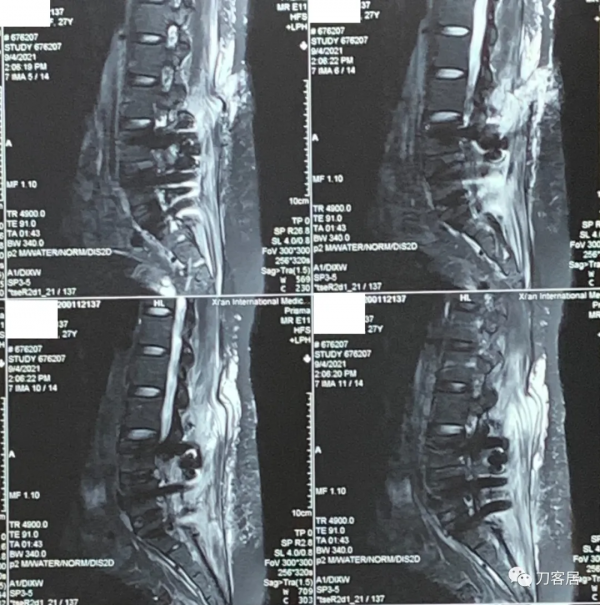

圖11. 20210904術後11天,腰椎MRI矢狀面T2相,可見切口內訊號混亂,切口內高訊號液性聚集。

圖12. 20210904術後11天,腰椎MRI矢狀面T2相,可見切口內訊號混亂,切口內高訊號液性聚集。

圖13. 20210904術後11天,腰椎MRI矢狀面T2相,可見切口內訊號混亂,切口內高訊號液性聚集。

圖14. 20210904術後11天,腰椎MRI矢狀面T1相,可見切口內訊號混亂,切口內液性聚集。

圖15. 20210904術後11天,腰椎MRI矢狀面T2相,可見切口內訊號混亂,切口內高訊號液性聚集。